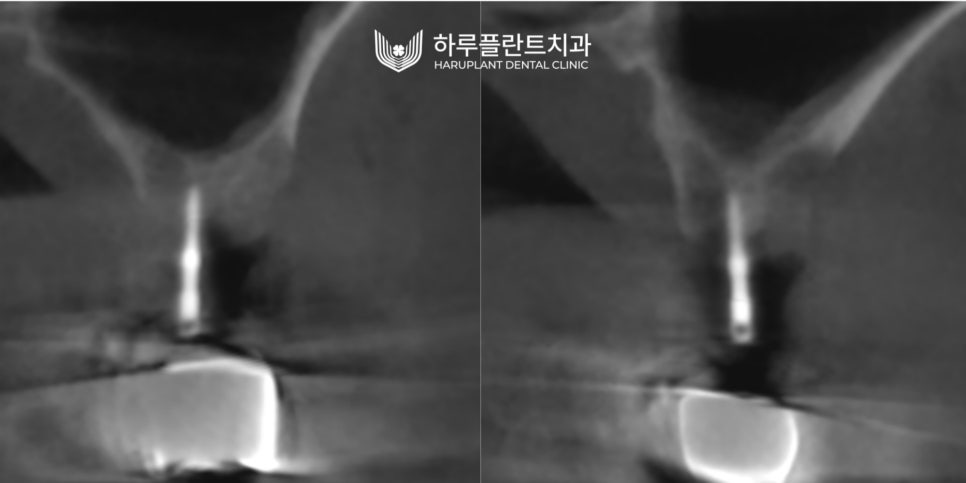

2023.02 ▲ 수술 전 CT 단면 (우측) / 수술 전 CT 단면 (좌측)

▲ 무절개 네비게이션 가이드 핀 삽입 후 (우측) / 무절개 네비게이션 가이드 핀 삽입 후 (좌측)

▲ 무절개 상악동 거상술과 동시에 임플란트 식립 (우측) / 무절개 상악동 거상술과 동시에 임플란트 식립 (좌측)